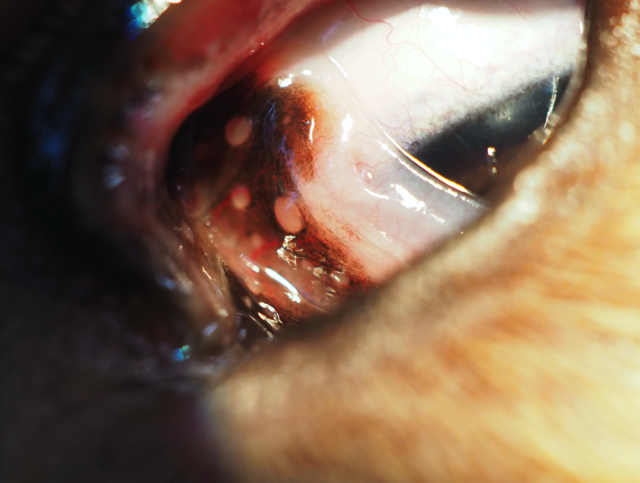

Semitransparente Follikel bilden sich hauptsächlich auf der Bulbusoberfläche der Nickhaut, sie können sich aber auch anderswo auf der Bindehaut sichtbar sein.

Die Follikel auf der Bulbusoberfläche der Nickhaut sind im Zuge dieser Erkrankung weitaus zahlreicher als normalerweise sichtbar und können deutlich größer sein. Häufig liegen gleichzeitig eine Hyperämie der Bindehaut und ein schleimiger Augenausfluss vor.